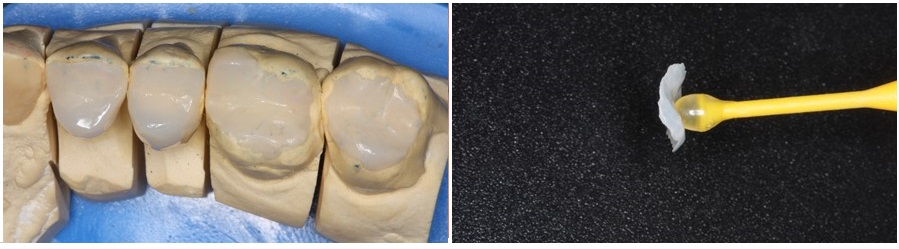

Στην φωτογραφία που ακολουθεί, βλέπουμε κάποιες από τις αποκαταστάσεις των πίσω δοντιών τοποθετημένες στο εκμαγείο και στην συνέχεια την εικόνα των οπίσθιων δοντιών πριν και μετά την συγκόλληση των αποκαταστάσεων στο στόμα.

Με την συγκόλληση των επένθετων στα πίσω δόντια, πετύχαμε την αύξηση της κάθετης διάστασης του προσώπου. Έτσι δημιουργείται χώρος για να κατασκευάσουμε στο αμέσως επόμενο στάδιο, μικρές αποκαταστάσεις από ρητίνη για την πίσω πλευρά των μπροστινών δοντιών.